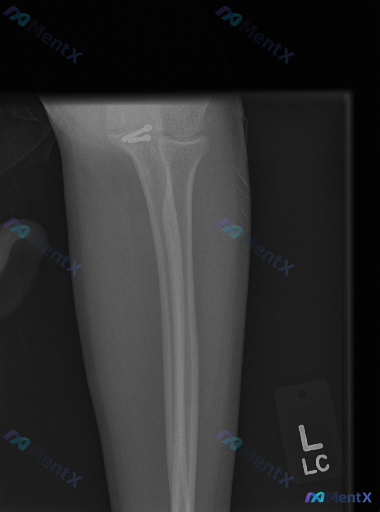

整理到一张左前臂(含肘关节)的X光复查片,先抛出来给大家看看。 影像里明确能看到的: 1. 尺骨和桡骨近段都有金属接骨板+多枚螺钉固定 2. 内固定物位置看起来还稳,没有明显断钉、松动或钢板断裂 3. 肘关节各个关节对位正常,间隙也清 4. 周围软组织没有明显肿胀 但有个细节有点意思: 接骨板覆盖的...

整理到一张左前臂(肘关节近端)的正位X光片资料。 影像基础信息: - 可见左侧桡骨近端(桡骨头/颈区域)有金属螺钉内固定物,位置大致固定,无明显松动或断裂 - 其余所见骨骼结构完整,未见明确新发骨折线/透亮线 - 肱桡、上尺桡关节对位尚可,间隙无明显增宽或狭窄 - 骨小梁纹理基本均匀,无明显骨质疏松...